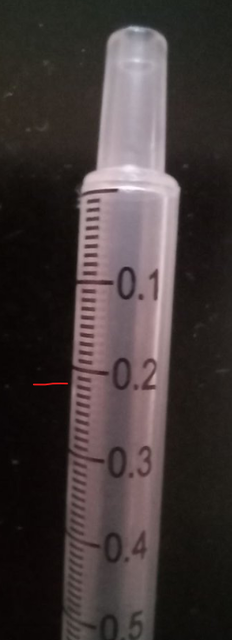

@DarthAlex 1. Уфа.26 лет мне и 11 лет крксноухой черепахе 2.Красноухая черепаха 3. Террариум. Месяц как на подоконнике стоит, раньше подсоединил комнаты стоял. И как только на окно поставили глаза отекли и не открываются. Привет рестартов на другой подоконник который не сразу в окно выходит, а на лоджию. Примерно около 70-90 литров аквариум с островком 4. нагреватель стоит для объема 60-90 литров, мощность 75. включаю лампу греющую 50W+uvb 3.0 (включаю с 8 утра и до 22-23:00) 3 недели как так работает, ранее включала раз в неделю на 2-3 часа уф лампа uvb 5.0, мощность 26вт(включаю с 8 утра и до 22-23:00) 3 недели как так работает, ранее включала раз в неделю на 2-3 часа артикул на вб на уф лампу: 332588948 Берег имеется, стеклянный фильтр имеется в аквариуме, внутренний, мощность 15вт артикул на фильтр вб: 241176284 Нагреватель воды имеется мощность 75. Артикул вб : 230910750 5. грунт имеется, Галька 8-12мм фракции 6. Температуру воды сейчас поддерживаем 27-29 градусов, температура на суше около дампы греющей 30 7. Кормила всегда только филе минтай или хек, без каких либо добавок. Кушает сейчас хорошо. Крайние два приема начала добавлять в рыбу витамины репаши витамин А 166427259 и фуд фарм кальций без д3 : 168761147 также добавила траву в аквариум крайний неделю, всю съела (фото приложу). Кормлю 1-2 раза в неделю 8. возраст 11 лет. Вес 0.41. Глаза отекли с 20.11.2025 года 9. 26 ноября 2025 года были на приеме у врача в Уфе. Рекомендация: 7-14 дней раствор рингера 10-12мл колоть (делаем уже 9 дней) , промыть глаза раствором натрий хлорид и через 20-30 минут капать по одной капле тобрамицин (3 раза в день делаем, 12-13 дней уже) также онлайн консультация другого врача покупала: посоветовала уменьшить дозу рингера до 0,8 и добавить 0,4 кальций глюконат (крайние 4 дня делаю именно так) также посоветовала Элеовит 0,2 сейчас (вчера сделала вынутримышечно) и через 2 недели повторить этот врач по снимку думает что тимпания и сказал стараться не кормить пока, а всё колоть а врач где были на оффлайн консультации предполагает пневмонию, и сказал кормить нужно с витаминами НО ЧЕРЕПАХА ХОРОШО КУШАЕТ И ОЧЕНЬ АКТИВНАЯ Также хотела добавить, что крайние 3 дня в момент укола черепаха начала писить, плохо ли это? Черепаха на левый бок всплывает, уже достаточно давно